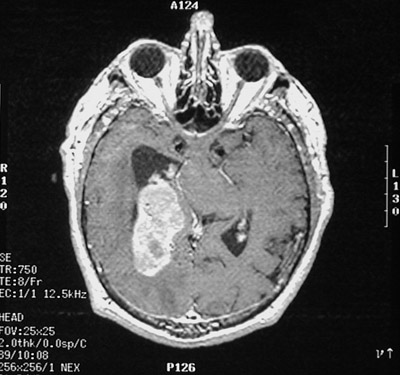

| This axial view MRI scan reveals a meningioma in an atypical location--near the lateral ventricle. About 3% of meningiomas may be located within the brain parenchyma, rather than over the surface. A tumor in such a location may mimic a metastatic lesion or an ependymoma. |